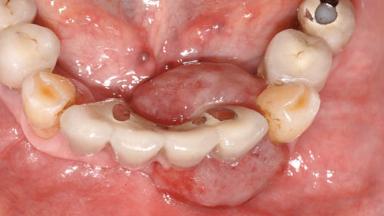

Peripheral Giant-cell Granuloma Associated with Peri-implant Tissues

Case Type Extended Space

Jaw Mandible

Area Anterior|Posterior

# of Teeth 10

# of Implants 5

Type of Implants One-Piece